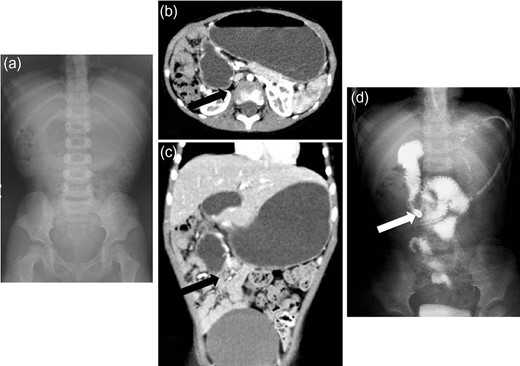

A 6-year-old girl presented with bilious vomiting and abdominal distension. She has Trisomy 18 and has undergone a tracheostomy and gastrostomy. Abdominal X-ray films showed dilatation of the bowel with gas (Fig. 1a). After injecting contrast medium through the gastostomy, retention of the contrast was noticed, which revealed intestinal obstruction. Based on plain computed tomography (CT) intestinal volvulus or intussusception was suspected (Fig. 1b and c). A barium enema revealed an incomplete obstruction or stricture (Fig. 1d). She underwent a laparotomy, and the intra-operative findings revealed a Meckel’s diverticulum, multiple intestinal tumors that were thought to be ectopic pancreas, and midgut volvulus associated with mesenterium ileocolicum commune and normal rotation of the intestine (Fig. 2a and b). Because of the massive content and gas in the bowel, a tube was inserted into the Meckel’s diverticulum to decompress the intestinal content. The midgut volvulus involved 180 degrees of counter-clockwise torsion, which was released with resection of the Meckel’s diverticulum and an appendectomy. Multiple intestinal tumors were resected, which were indeed diagnosed as ectopic pancreas. At one month post-operatively, she underwent adhesiolysis due to an ileus. She is currently doing well without torsion of the intestines.

Radiologic findings from Case 1. (a) Abdominal X-ray films showing dilatation of bowel with gas. (b and c) Plain computed tomography showing suspected intestinal volvulus or intussusception (white arrow: suspected lesion). (d) Barium enema revealing an incomplete obstruction or stricture (black arrow: suspected lesion).